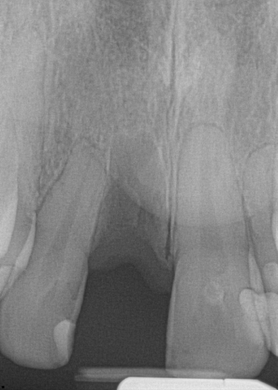

Every dentist has had to make a diagnosis based on the evidence presented during a patient's visit. Traditionally, a periapical radiograph was the line of choice. Changing from film x-rays to digital imaging with 3D cone beam computed tomography (CBCT) has enhanced the dentist's ability to more rapidly and efficiently diagnose (Figure 1). Now, the merging of digital photographs, intraoral scanning, and 3D CBCT data can be delivered to the dental laboratory electronically and ready for prosthetic and surgical treatment planning based on the patient-specific 3D data set taken in one visit at the dental practice. This complete 3D digital patient-specific record creates a hard and biomechanical foundation for accurate 3D planning.8

Fig 1. 3D CBCT imaging.

Figure 1

Fig 16. Preoperative periapical radiograph on the day of surgery.

Figure 16